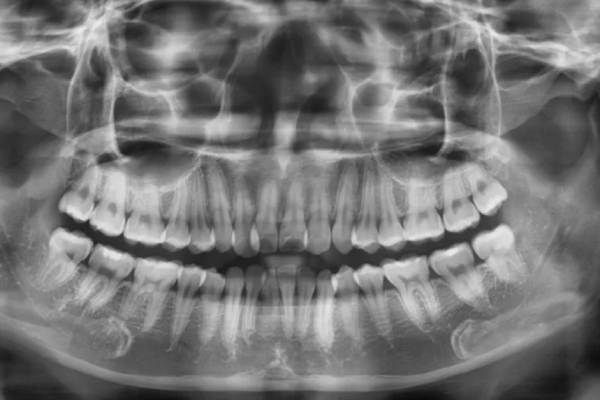

Trám răng thẩm mỹ là gì? Có những loại nào? Lưu ý gì?